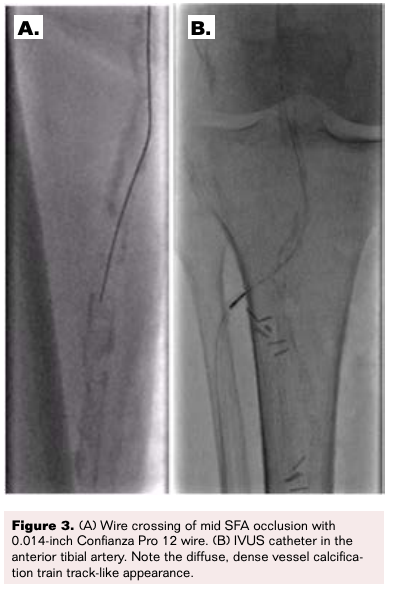

The patient was evaluated and a shared decision was made to proceed with a repeat intervention attempt to revascularize her leg in an attempt to prevent amputation and relieve her symptoms. She was promptly taken to the catheterization laboratory. Antegrade access was obtained under ultrasound guidance using a micropuncture access set (Cook Medical), and up-sized for a 6Fr x 10 cm Pinnacle sheath (Terumo Interventional Systems). Therapeutic anticoagulation was administered and activated clotting time (ACT) was maintained at more than 200 seconds. Digital subtraction angiography of the right lower extremity with runoff was obtained (Figure 2).

A 0.018-inch Gladius wire (Asahi) was used with an 0.035-inch Quick-cross support microcatheter (Philips); however, the lesion could not be crossed. Next, a 0.014-inch Confianza Pro 12 wire (Asahi) was chosen for its greater penetrance through which successful antegrade crossing of the mid SFA CTO was established. However, the Quick-cross microcatheter could not advance. This was switched to a 0.014-inch Corsair Pro microcatheter (Asahi), which was spun and advanced successfully to the distal popliteal occlusion. The 0.014-inch Confianza Pro 12 wire was used again to cross the second calcified CTO lesion, with careful attempts to remain intraluminal, and subsequently switched to a 0.014-inch Choice PT extra support guidewire (Boston Scientific), then advanced down the anterior tibial artery to the dorsalis pedis artery (the posterior tibial artery had been ligated proximally) (Figure 3A).

IVUS imaging was performed next, revealing extensive, circumferential intimal and medial calcifications of the tibial, popliteal and femoral vessels with no evidence of significant vessel dissection (Figure 3B, Figure 4).